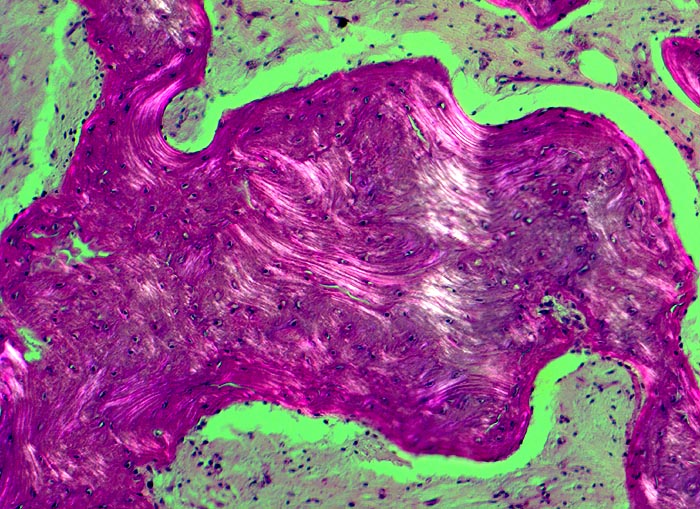

Morbus Paget des Knochens

Knochen, Tibia

In der Doppelbrechung wird die unregelmässige mosaikartige Struktur der Spongiosabälkchen besonders deutlich.

Die Patientin hatte wiederholt über Knieschmerzen geklagt. Autoptisch zeigte das Kniegelenk eine leichte Arthrose. Aus der auffallend verdickten Tibia wurde eine Gewebsprobe zur Untersuchung entnommen.